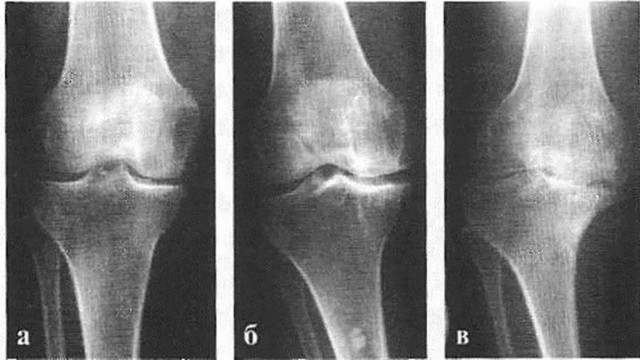

Стадии болезни

Различают три (иногда – 4 и даже 5) стадии остеоартроза.

Начальная стадия

Стадия остеофитов

Хрящи и мениски начинают разрушаться, боль возникает при обычной физической нагрузке и сама не проходит, снимается анальгетиками. Сустав увеличивается, нарушается его форма и подвижность. Размер суставной щели на рентгеновском снимке заметно уменьшен, видны явные костные разрастания. Поверхность сустава изменена (на снимке – просветления в кости).

Тяжелый артроз

Беспокоят постоянная боль, стойкая деформация суставов с нарушением оси конечности, резкое ограничение подвижности. Из-за вынужденного бездействия в определенных группах мышц развивается атрофия, может измениться длина конечности. При рентгенологическом исследовании суставная щель не визуализируется. Поверхность сустава изменена, видно обширное разрастание остеофитов, наблюдаются явные кистозные просветления в кости.

Деформация возникает за счет отека суставной сумки, разрастания остеофитов. При нарушении формы коленных суставов образуется Х- или О-образная деформация ног (рис. 4). При остеоартрозе пястно-фалангового сустава большого пальца стопы формируется пресловутая «косточка», которая уродует ногу и причиняет дискомфорт.

О возможности наличия артроза говорят: